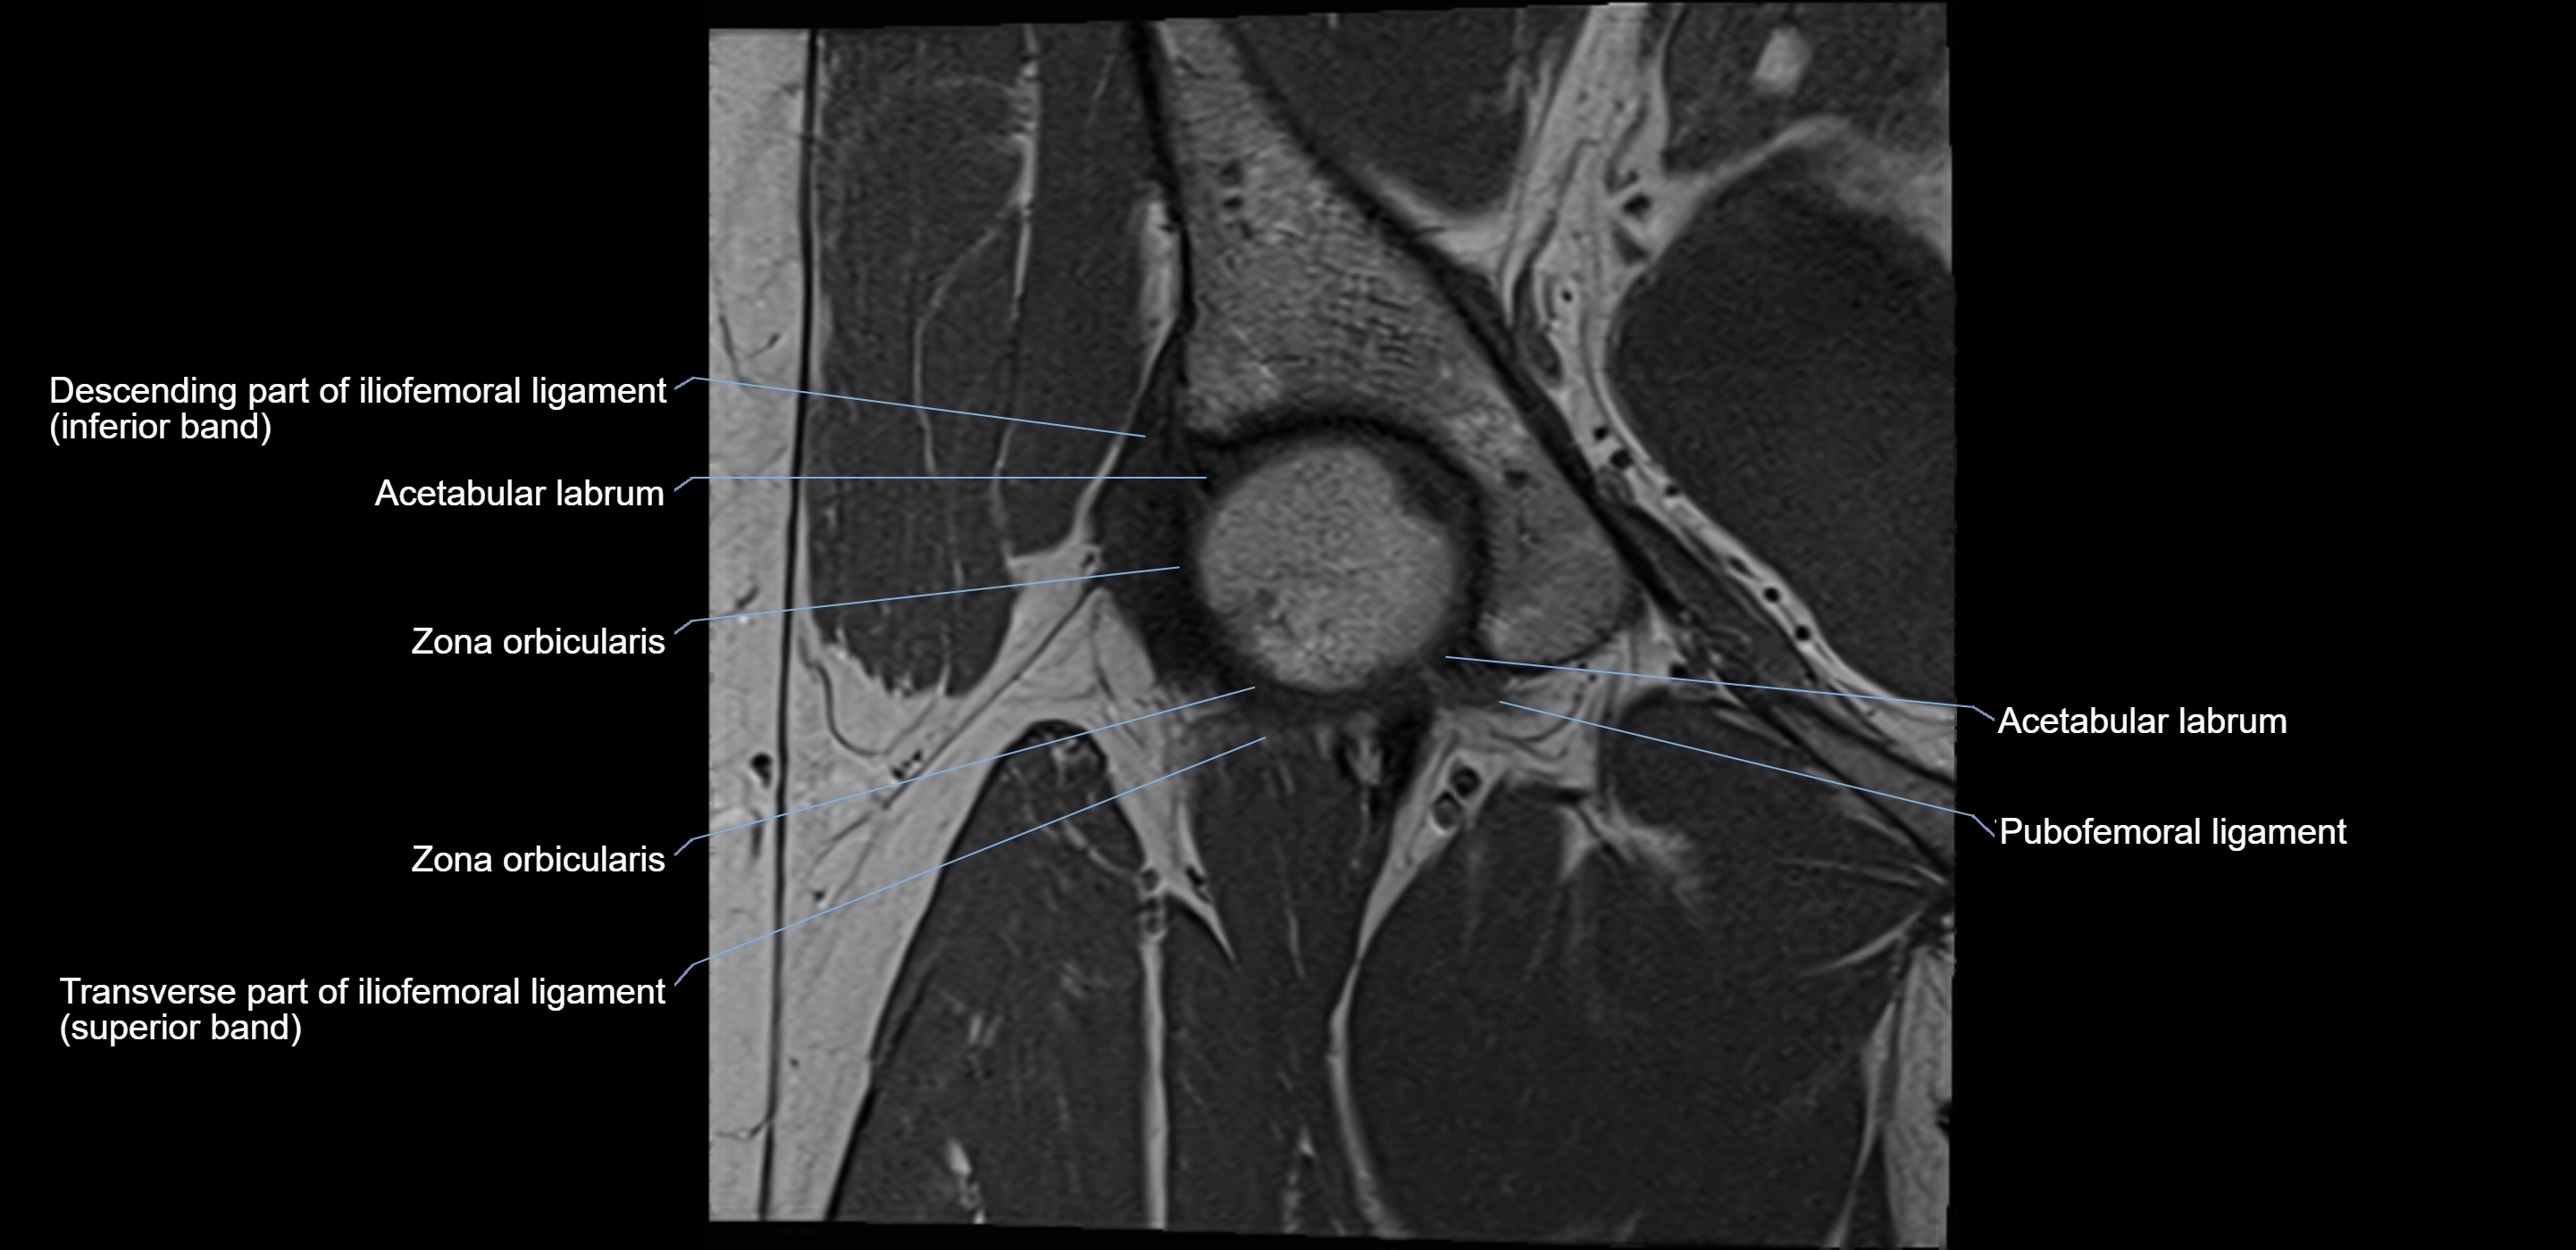

MRI Appearance

T1-weighted images:

• Labrum: low signal intensity (dark)

• Surrounded by intermediate signal joint fluid (bright on arthrogram)

• Tears: linear or focal areas of intermediate-to-high signal interrupting labral continuity

T2-weighted images:

• Joint fluid: bright, making labral tears visible as fluid extending into or around labrum

• Degeneration: may show areas of increased signal within labrum

MRI image

image